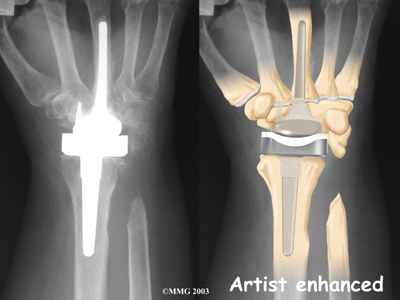

The main reason for replacing any arthritic joint with an artificial joint is to stop the bones from rubbing against each other. This rubbing causes pain. Replacing the

with an artificial joint gives the joint a new surface, which lets it move smoothly without causing pain.

Many operations are used to treat problems in the wrist. A can get rid of pain and restore strength in badly degenerated wrist joints.

Fusion surgeries make the wrist strong again, but they greatly reduce the wrist's range of motion. This makes fusion surgery a poor choice for some people.